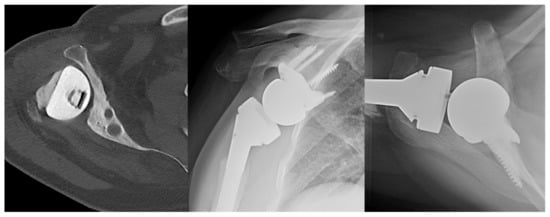

Augmented Glenoid Components

5.1. Patient-Specific Instrumentation and Pre-Operative Planning